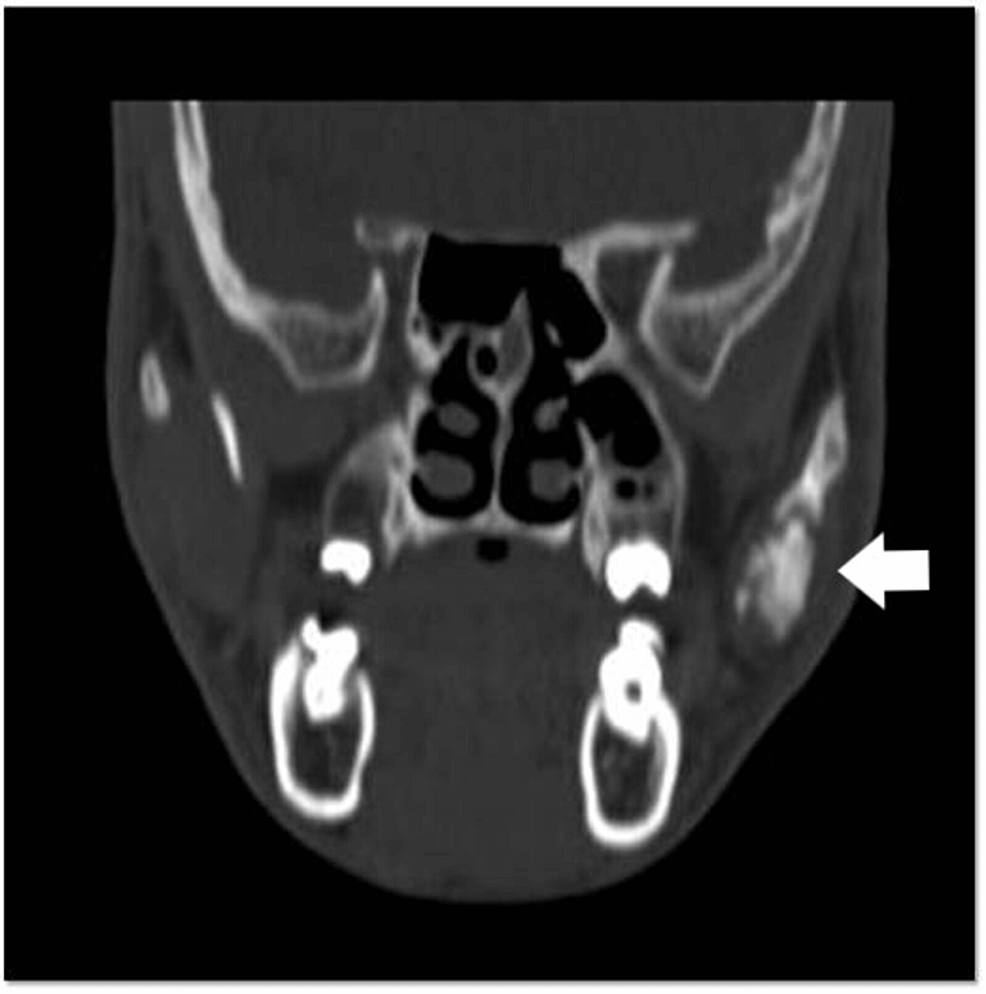

From www.researchgate.net

Computerized tomography images of left isolated zygomatic arch fracture Zygomatic Extension Definition It extends from the temporal bone in the skull to the. It is often referred to as the cheekbone, and it comprises the prominence just below the lateral side of the. The zygomatic arch is located in the middle of the face, just below the eye. The zygomatic arch, cheek bone, or zygoma are all interchangeable terms for the structure. Zygomatic Extension Definition.